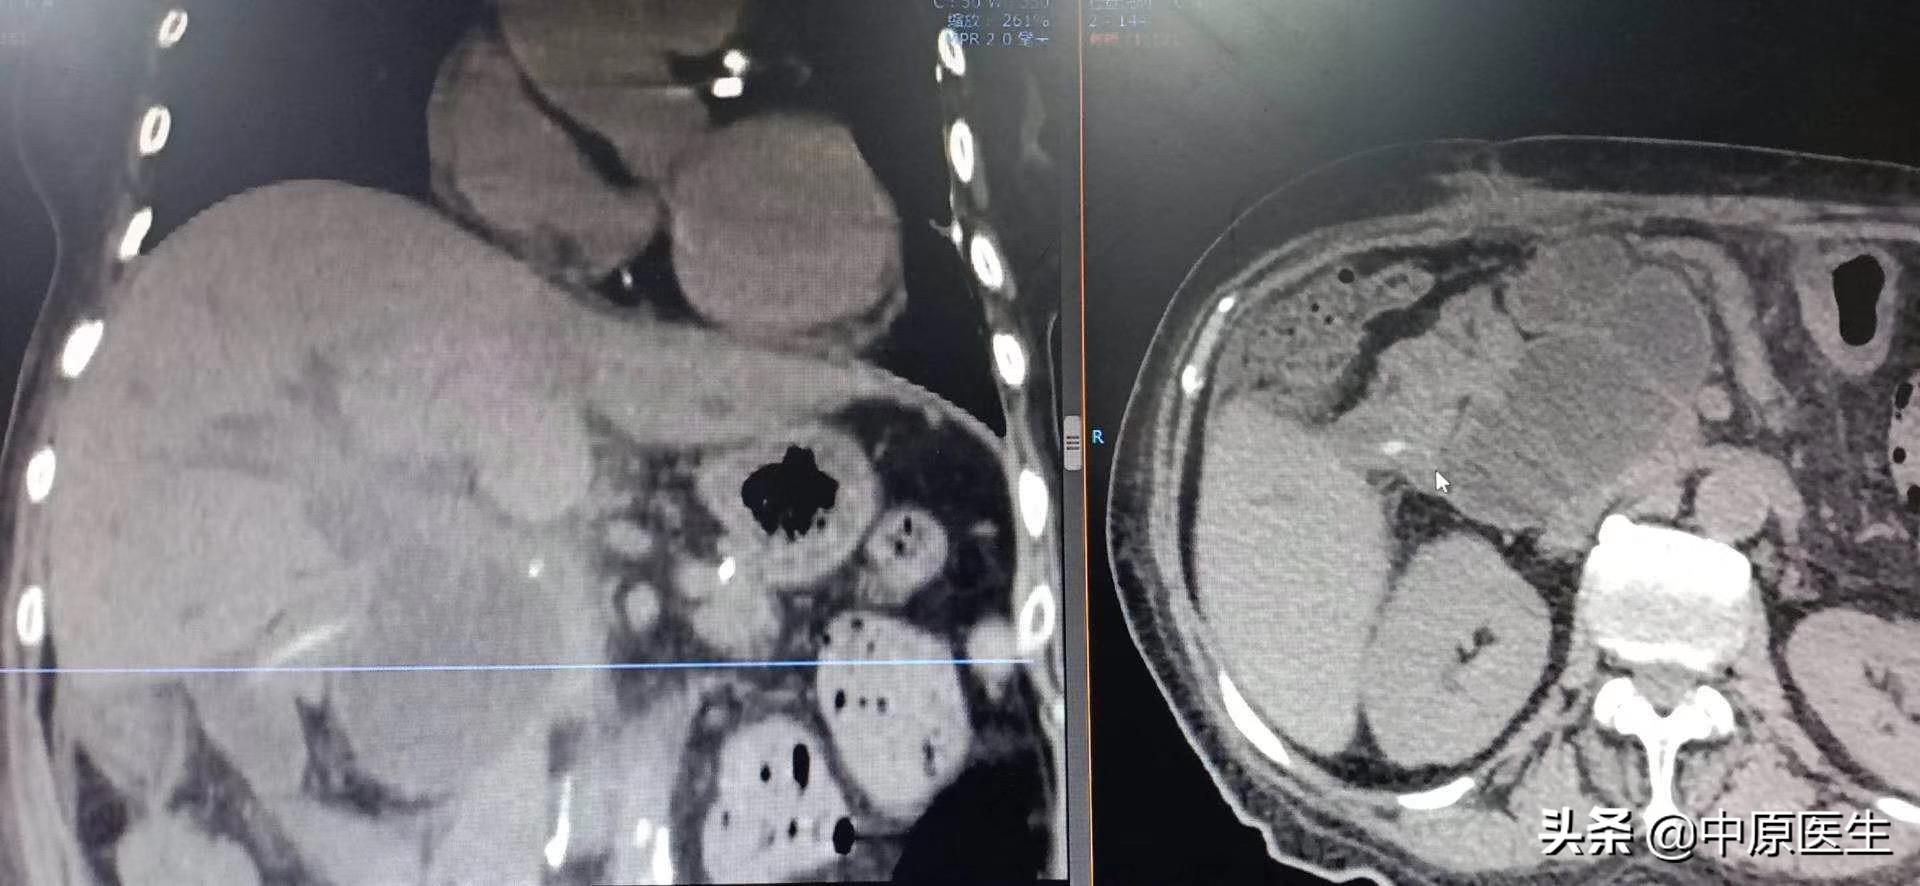

这是一个胰十二指肠切除术后的老太太、曾经做过胆肠吻合,肠管狭窄导致严重胆管梗阻和感染的病人,虽然经过内科规范治疗,仍然反复高热,感染无法控制。

经过消化内科多位专家,肝胆外科专家还有我们介入科专家共同会诊,建议找我做经皮穿刺胆管引流术(PTCD)、肠管狭窄球囊扩张术。

经过我认真查阅检验结果和影像资料,发现血培养结果:屎肠球菌、阴沟杆菌双细菌感染,多种抗生素耐药;有电解质紊乱。查看患者,体质极度衰弱,这就是合并了梗阻性化脓性胆管炎,一个要命的急症!通过十二指肠镜做ERCP?镜子过不去!再做外科手术?无论是患者的状态,还是局部解剖结构的紊乱,都很难实施!我与家属反复交代了介入治疗手术操作的方法、风险等,并且签署了手术协议书。

经过消化内科积极准备,病人当天晚上就躺了我们的术台上,那时的患者,正在寒颤,我们迅速消毒,铺巾,准备好手术器械,定位、局麻,从右侧胸壁腋中线第十肋间一针穿刺进入肝右胆管,依次送入扩张鞘,导丝,外引流管,随即就抽出了瘀滞的带味道(感染细菌发出来的味道)的墨绿色、带沉渣的胆汁和肠液约100多毫升。因为患者寒颤,身体情况太差,所以我们放弃了再仔细寻找狭窄肠管部位的手术(这时候保命要紧,那个手术可以择期再次进行),冲洗引流管后,固定、包扎。把患者安全转入介入科病房。回到病房十多分钟后,患者的腹胀、寒颤都有了明显减轻。精神状态也好了很多。看着自家老人转危为安,这一家子说了数不清感激的话!

我们做这个经皮穿刺胆管造影+引流管置入术(PTCD)是怎么一回事呢?它是在影像设备引导下,用一根21G(0.80mm)的细穿刺针经皮经肝穿刺胆管,并置入引流管,使胆汁流向体外或十二指肠的一系列技术。主要用于胆道梗阻和急性炎症的治疗。PTCD不受胆管手术影响(如胆肠吻合术等),对患者的身体要求相对较低,创伤小,缺点是对原发病的治疗有时候会力不从心。